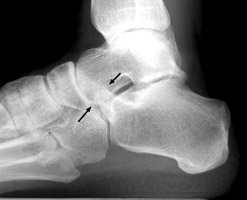

Calcaneonavicular coalition

Plain film and CT images of calcaneonavicular coalition. Notice the elongated, tubular like extension of the anterior calcaneus seen on the lateral film; this imagery has been likened to the elongated nose of an anteater. There is abnormal bony fusion of the calcaneus and navicular bones, with the presence of a bony bar extending between these two bones.

bulletOestreich AE, Mize WA, Crawford AH, Morgan RC Jr.: The "anteater nose": a direct sign of calcaneonavicular coalition on the lateral radiograph. J Pediatr Orthop 1987 Nov-Dec;7(6):709-1.          [See related articles]